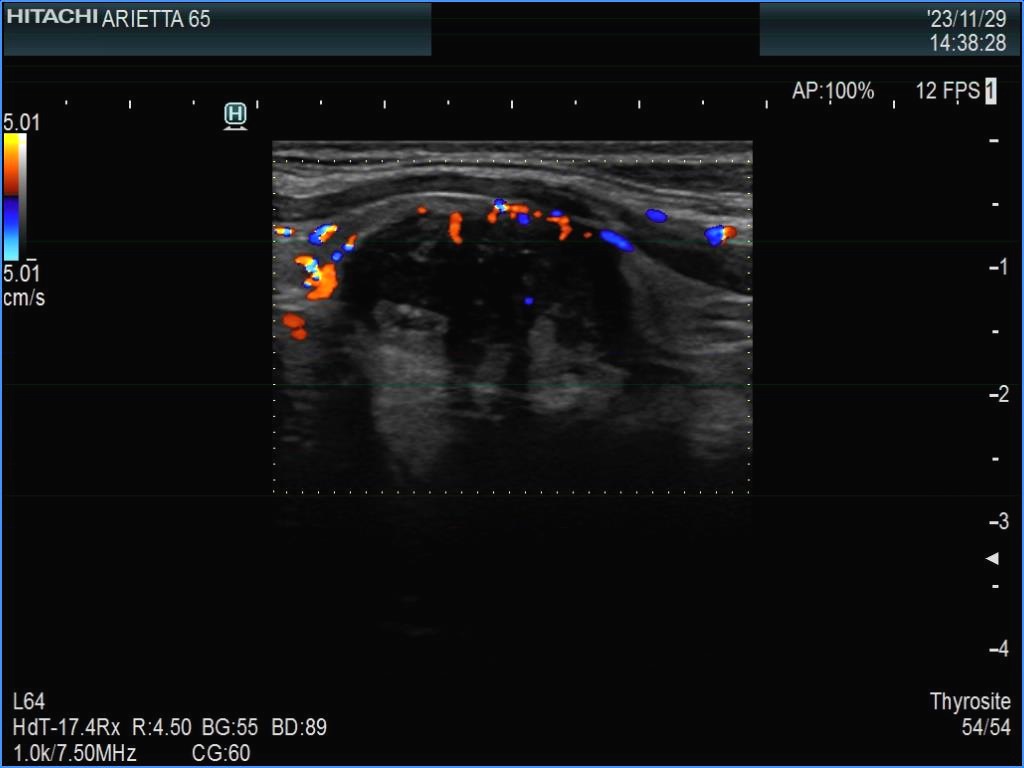

Ultrasonography. The thyroid was echonormal. There were multiple smaller lesions in the right lobe. The largest one was minimally hypoechoic and presented with halo and perinodular vascularity. A large, hypoechoic nodule occupied almost the entire left lobe. The nodule had lobulated and spiculated margins and bulged into the sternocleidomastoid muscle. The vascularity was not specific.